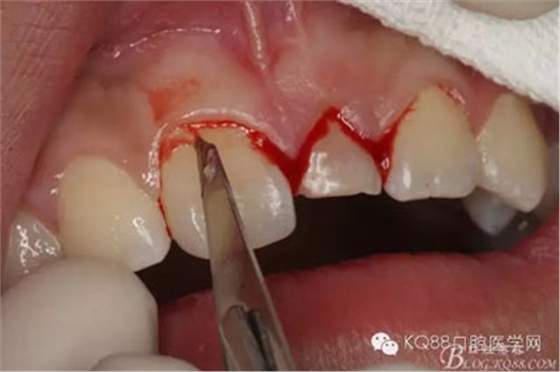

圖4.腭側(cè)觀:左乳Ⅰ腭側(cè)牙齦正常,無松動,擬摘除牙瘤,暫時保留左乳Ⅰ。

圖5.局部無痛麻醉下。行唇側(cè)齦溝內(nèi)切口